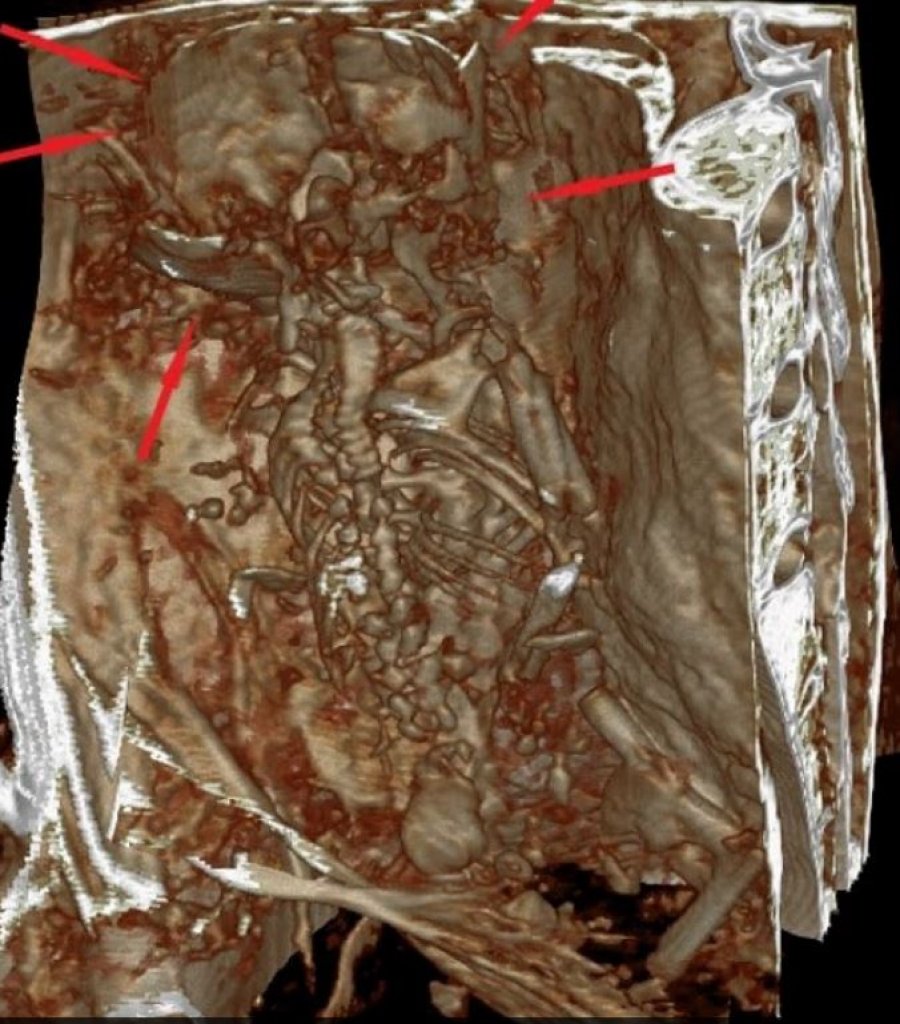

Figurat e botës tjetër u zbuluan më vonë se kishin implante metalike në duart e tyre me tre gishta dhe koka të zgjatura.

Ekipi vlerësoi se Montserrat vdiq midis moshës 16 dhe 25 vjeç. Ajo ishte afërsisht 1.60 metra e gjatë dhe kishte implante në duar, gjoks dhe kokë.

Sipas studiuesve, implantet duket se kanë një dendësi të ngjashme me metalin.

Një objekt i dukshëm në kokën e Montserrat duket se është implantuar, ndërsa ajo ishte ende gjallë, sipas shkencëtarëve, të cilët vunë re se lëkura duket se është rritur rreth implantit.

Ekipi zbuloi gjithashtu pllaka metalike në të gjithë trupat e mumjeve të tjera, disa të vendosura brenda, duke mbuluar kockat dhe të tjera të bashkangjitura nga jashtë në lëkurë.

Këto implante duket se janë ‘biofunksionale’, pasi nuk tregojnë shenja refuzimi nga trupi.

“Këto pllaka polimetalike u analizuan duke përdorur teknika matjeje të bazuara në dritë, dhe u zbulua se përmbanin një aliazh bakri, kadmium, osmium, alumini, ari dhe argjendi”, tha Dr. Zalce.

“Vlen të përmendet se argjendi është mbi 95 përqind i pastër, një gjë e rrallë në natyrë. Kadmiumi dhe osmiumi, të dy zbulime relativisht moderne, janë materiale që përdoren aktualisht në komunikimet satelitore dhe strukturat hapësinore.”